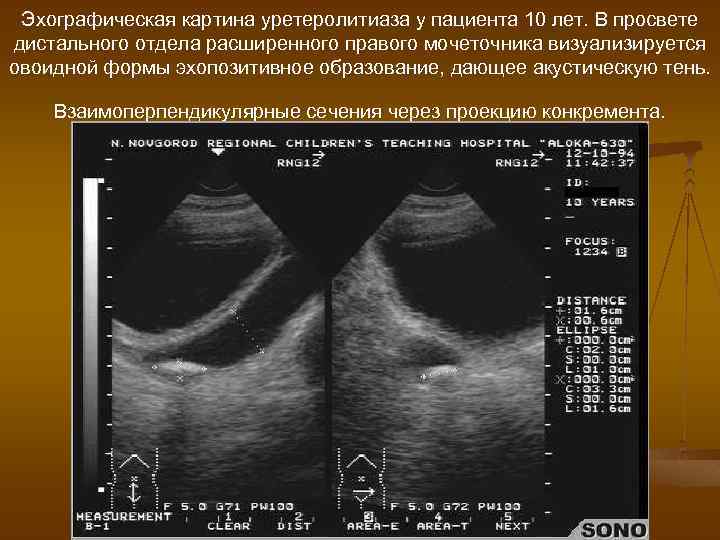

Эхографическая картина уретеролитиаза у пациента 10 лет. В просвете дистального отдела расширенного правого мочеточника визуализируется овоидной формы эхопозитивное образование, дающее акустическую тень. Взаимоперпендикулярные сечения через проекцию конкремента.